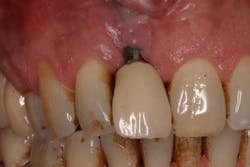

Fig. 1: Soft tissue recession around a dental implant restoration due to a deficiency in soft tissue volume.